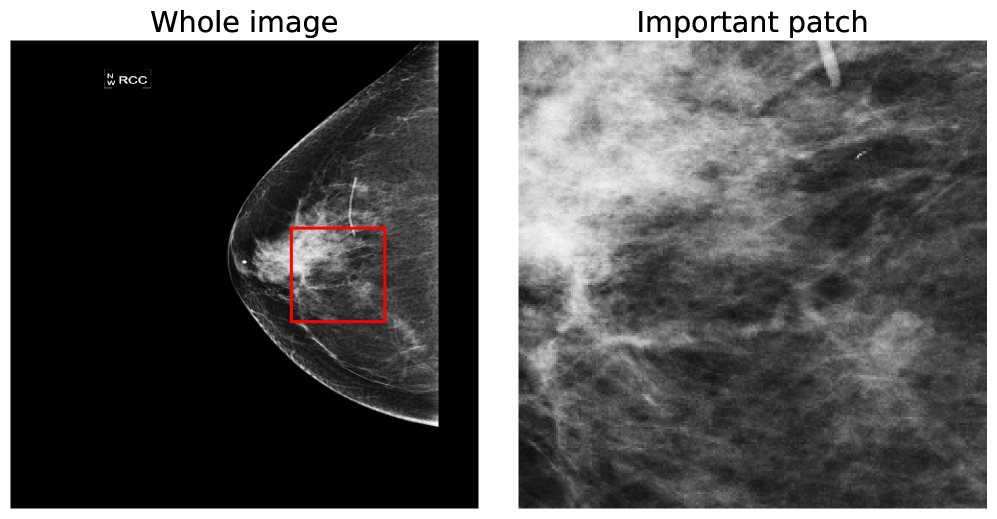

A further benefit of our approach is that the concept vectors can be used to gain an interpretable component about what the model is learning to look for. We can do this by showing example patches that correspond to the ’th concept vector activating and having the maximal response, i.e., making the classification determination. We provide an example for the first five concept classes on the BTMD dataset in Figure 4 and the RSNA-SMBC dataset in Figure 5. In both cases, the row corresponds to a concept, and 25 columns show 25 winning exemplars.

The BTMD dataset has considerably more visual variation in the images, making them more challenging to inspect as non-medical experts, but visual themes are generally discernible across each row in Figure 4. We note that there is no mechanism to force one concept vector to suppress other concept vectors for similar activations, and so we see some cross-pollination between the concept vectors. The RSNA dataset has less visual asperity, and visual patterns are more clearly observed in the rows of Figure 5.

In Figures 7 and 8, we display more representative patches selects that correspond highly to a given concept vector (one concept per row), highlighting our our method automatically learns sub-regions of the larger image space.